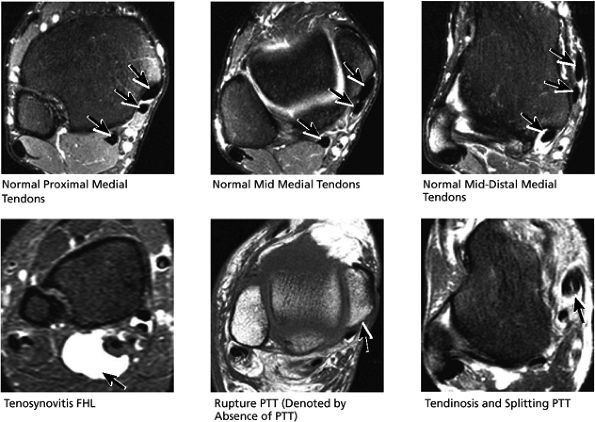

FIGURE 5.50 Medial Tendons.